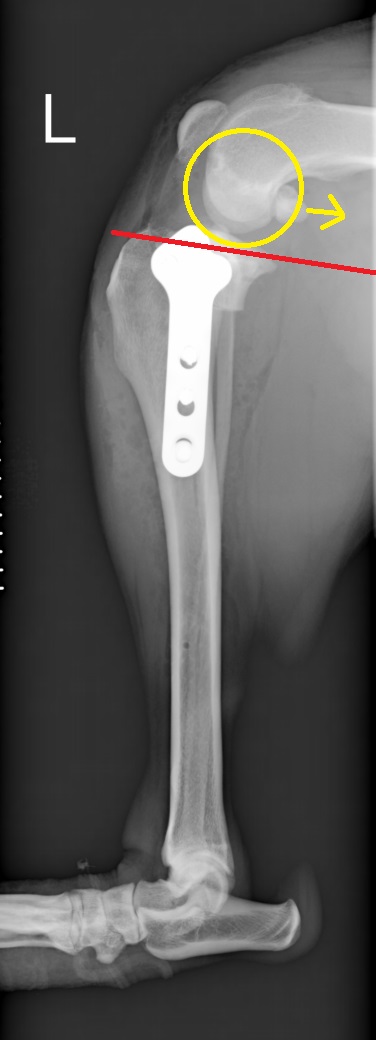

赤直線が脛骨高平部角、青・黄色矢印は大腿骨が滑り落ちてしまう力のベクトル

前十字靭帯損傷の膝。大腿骨が尾側に滑り、脛骨の前方変位が認められる

術後、脛骨高平部角がほぼなくなったことが分かります